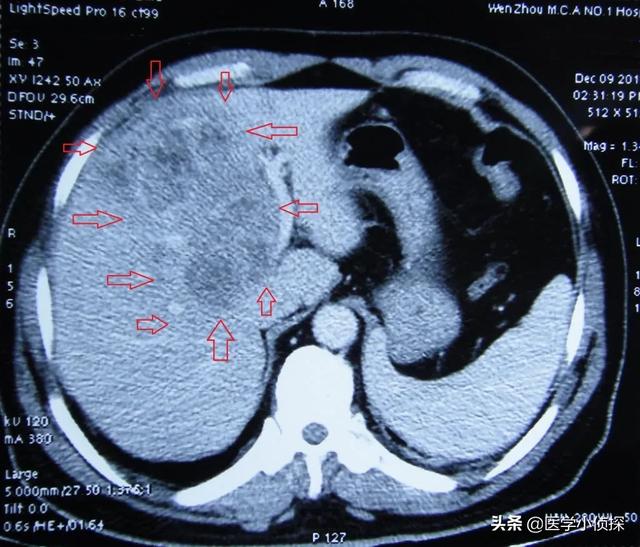

- 肝臓の超音波検査で肝臓に腫瘍が見つからない場合、または腫瘍の性質が判断できない場合、αフェト蛋白の上昇は肝細胞癌の可能性を強く疑わせる。さらに肝臓のCTを行うこともある。強化CTは肝臓腫瘍の特定に比較的優れているので、すぐに肝臓の強化CTをお勧めします。

- 肝臓の強化CTは肝臓癌の診断に一定の利点があるが、対応する放射線の存在により身体に一定の害をもたらすので、苦手な人は放射線の害がなく、肝臓の病変を明瞭に見ることができる肝臓の核磁気検査を受けることができる。